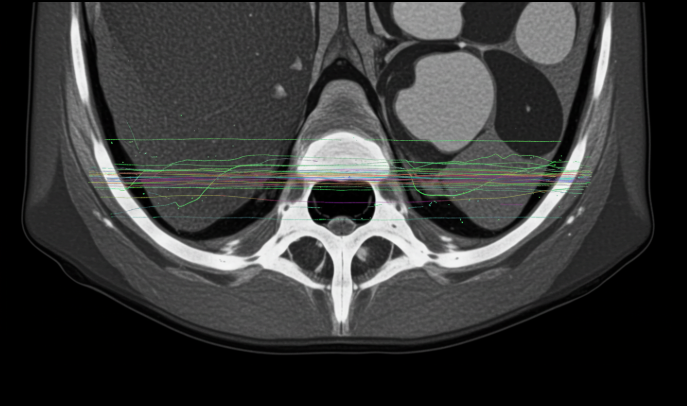

CT 검출기는 몸을 통과한 X선 에너지를 수신해 디지털 신호로 변환하는 역할을 합니다. 이 핵심 부품이 정상 작동하지 않으면 다음과 같은 문제가 발생할 수 있습니다. 1. 영상 왜곡(Image Artifact) 검출기의 일부가 신호를 제대로 받지 못하면 영상에 줄무늬, 어두운 띠, 왜곡 현상이 생깁니다. 이러한 영상 왜곡은 병변을 가리거나, 오진의 원인이 될 수 있습니다. 2. 감도 저하(Sensitivity Loss) 검출기의 성능이 떨어지면 미세 병변을 놓치게 됩니다. 특히 초기 암, 미세 혈관 이상 같은 질병은 초기에 발견하지 못할 위험이 커집니다. 3. 반복 촬영 필요 영상 품질이 기준 이하일 경우 재촬영을 해야 합니다. 이는 환자의 불필요한 방사선 노출을 증가시키고, 검사 비용과 시간 낭비로 이어집니다. 4. 진단 지연 또는 오류 검출기 오작동으로 인한 영상 품질 저하는 진단 정확성을 크게 떨어뜨려, 환자 치료에 치명적인 영향을 줄 수 있습니다. CT 검출기의 정상 작동 여부는 단순한 장비 문제가 아니라, 환자 안전과 진단 품질을 직접 좌우하는 매우 중요한 요소입니다.

CT 검출기 오작동은 전 세계적으로 다양한 사례가 보고되었습니다. 대표적인 사례를 통해 구체적으로 살펴보겠습니다. 1. 검출기 픽셀 불량에 의한 영상 왜곡 어느 대학병원에서는 CT 검출기 일부 픽셀에 고장이 발생해 영상에 선명한 줄무늬(스트라이프 아티팩트)가 생겼습니다. 이로 인해 초기 뇌경색을 놓칠 뻔했으며, 다행히 재촬영 후 제대로 진단할 수 있었습니다. 2. 검출기 센서 감도 불균형 한 종합병원에서는 검출기 센서 중 일부가 노후화되면서 영상의 밝기 균일성이 떨어졌습니다. 이로 인해 조기 간암 스크리닝 결과가 왜곡되어, 추가 검사가 필요했던 사례가 있었습니다. 3. 검출기 접속 불량으로 인한 데이터 손실 대형 병원에서 고해상도 CT를 운용하던 중, 검출기와 신호처리부 연결 부위의 접촉 불량으로 데이터 일부가 손실되었습니다. 결국 검사 데이터를 사용할 수 없어 전체 촬영을 다시 진행해야 했습니다. 4. 소프트웨어 오류와 검출기 오작동 검출기 자체는 문제가 없었지만, 소프트웨어 업데이트 오류로 인해 검출기 신호 해석이 잘못되어 영상에 왜곡이 발생한 사례도 있었습니다. 이처럼 검출기 오작동은 기계적 고장뿐만 아니라, 소프트웨어, 연결 부품 문제 등 다양한 원인으로 발생할 수 있으며, 항상 주의 깊은 점검과 관리가 필요합니다.